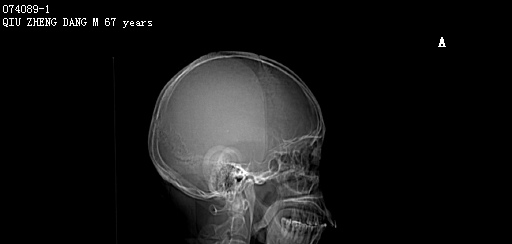

CT51360:M,67y。头晕一周。

本帖最后由 cefcmj 于 2015-12-1 20:32 编辑 男,67岁。头晕一周。PE:神清,四肢活动可。临床诊断:脑动脉供血不足。 现行头部CT平扫,图像如下:

左侧小脑可见类圆形较高密度影,内见低密度,考虑血管瘤伴血栓形成可能。

左侧小脑海绵状血管瘤

考虑左侧小脑海绵状血管瘤。

考虑 左侧小脑海绵状血管瘤伴出血。

左侧小脑血管母细胞瘤并出血?